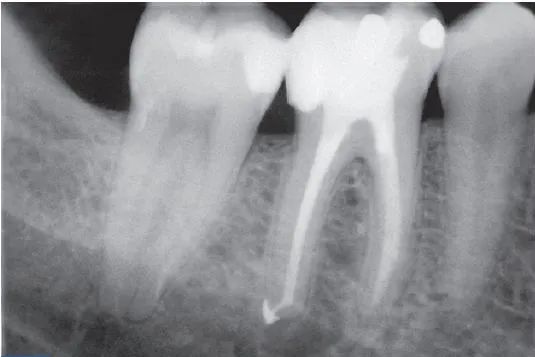

牙髓摘除法 -最好方法

方法一(选择性拔髓):前牙:开髓、拔髓、干燥根管,ZOE封丁香油棉捻。后牙:开髓揭髓顶,去除冠髓组织,对根管粗大(如上颁磨牙腭侧根,下颌磨牙远中根)则尽量拔髓,然用肾上腺素棉球止血后,用直径约1mm三聚甲醛失活剂置根管口,外加OC棉球,ZOE暂封,1周后复诊。

一次性拔髓根管内封药,对急性牙髓炎的止痛效果最好,拔髓后封药既去除了致痛的根本原因,使患者的病痛得到完全缓解,又避免了髓腔的再次感染,使以后的治疗效果更加理想。实际操作中,单纯拔髓难以去除全部牙髓组织,特别是根髓,结合根管扩锉与清理,同时减少复诊次数。

理论上急性牙髓炎应急治疗最好方法应是去除患牙全部牙髓组织,但在临床操作过程中,因根管系统复杂性(如狭窄,钙化等)及局麻质量,操作时间问题,往往出现拔髓不全,牙髓组织残留现象,这增加了治疗复杂性,封髓法及后牙选择性拔髓法,用药安全,止痛效果相对单纯开髓引流好,操作相对省时,值得临床推广。

在急性牙髓炎时应尽量去除炎性牙髓组织,在前牙,采用牙髓摘除术,然后密封开髓孔;在后牙,急性牙髓炎时炎症局限于冠髓,应急处理时去除炎性冠髓并封失活剂。急性牙髓炎合并根尖周炎时,炎症已波及根髓,应急治疗时前后牙均采取牙髓摘除术,ZOE封药。